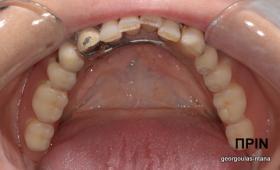

Η ασθενής αυτή είχε παλιές ακίνητες αποκαταστάσεις (γέφυρες) στην άνω γνάθο  κ μια κινητή προσθετική αποκατάσταση (μερική οδοντοστοιχία-"μασελάκι") στην κάτω γνάθο. Ήταν δυσαρεστημένη τόσο με την εμφάνιση όσο και με τη λειτουργία των δοντιών της καθώς παραπονιόταν ότι  είχαν εντονη κινητικότητα ενώ και οι προσθετικές τους εργασιές δεν ήταν σταθερές. Η πρόγνωση των δοντιών κρίθηκε φτωχή με αποτέλεσμα να μην είναι δυνατή η συμμετοχή τους σε μια νεα προσθετική αποκατάσταση με μακροχρόνια διάρκεια. Η ασθενής επιθυμούσε οι νέες αποκαταστάσεις να είναι σταθερές και ακίνητες.  Για το λόγο αυτό αποφασίστηκε η ολική αποκατάσταση της άνω κ κάτω γνάθου με ακίνητες επιεμφυτευματικές εργασίες. Στην αριστερή πλευρά της άνω γνάθου, λόγω μη επαρκούς οστού για την τοποθέτηση εμφυτευμάτων προηγήθηκε επέμβαση ανοιχτής  ανύψωσης ιγμορείου άντρου με τη χρήση πιεζοχειρουργικού μηχανήματος ώστε να δημιουργηθεί το κατάλληλο οστικό υπόστρωμα. Ακολούθησε σε επόμενο χειρουργείο η εξαγωγή των υπάρχοντων δοντιών κ η άμεση τοποθέτηση εμφυτεύματων (άμεση εμφύτευση) κ δύο μέρες μετά η τοποθέτηση προσωρινής εργασίας επί των εμφυτευμάτων (άμεση φόρτιση) με αποτέλεσμα η ασθενής να μη μείνει καθόλου χωρίς δόντια κ να είναι καλυμένη αισθητικά όσο καιρό διήρκησε η εργασία